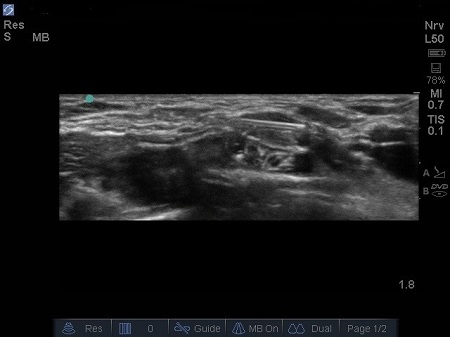

- It may sometimes be necessary to reposition the needle to ensure an adequate distribution of the LA (the entire plexus is surrounded by LA). See Fig. 8.

Fig. 8. Needle withdrawn and re –directed over the superior aspect of the brachial plexus, LA deposited to surround brachial plexus.

- If anaesthesia is intended for the distal upper limb, aim to spread LA in the corner bordered by the subclavian artery medially, the first rib inferiorly, and the divisions of the brachial plexus superior laterally (“the corner pocket”, and the ulnar nerve in this position would be “the 8-ball”) (6) (7).